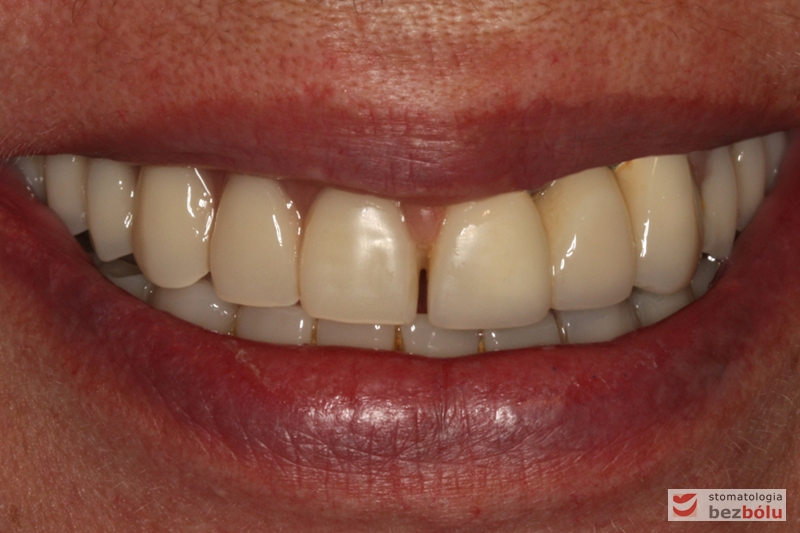

Ostateczny efekt terapeutyczny - zadowolona i uśmiechnięta pacjentka

Ostateczny efekt terapeutyczny – zadowolona i uśmiechnięta pacjentka